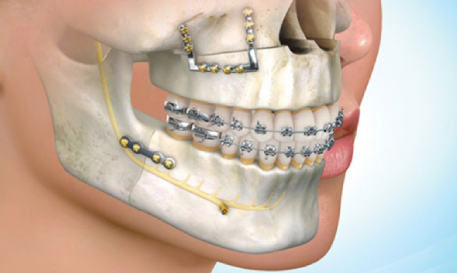

Maxillofacial Surgery

Comprehensive surgical care for facial and jaw conditions, performed with precision and advanced technology.

- Wisdom Tooth Removal

- Major & Minor Surgeries: (Trauma / Fracture / Apicectomy / Cyst / Abscess) Corrects fractures and infections effectively and restores the function and aesthetics of facial structures.